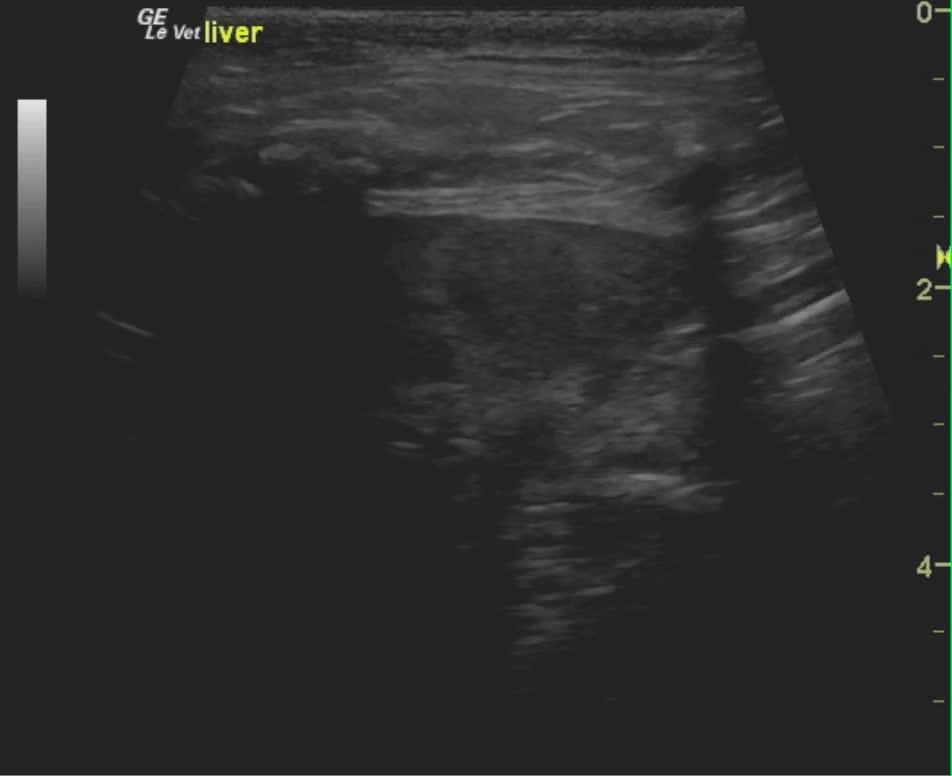

A 9-year-old MN DSH was presented for evaluation of lethargy, inappetence, and diarrhea. On physical examination, moderate dental tartar, poor body condition (BCS 2/5) and a dull unkempt hair coat was evident. On urinalysis moderate leukosuria, mild hematuria, and normal SG with moderate leukocytes, 2+ protein, 6.5 pH, urine specific gravity 1.035 with a small amount of blood. Abnormalities on CBC and serum biochemistry were neutrophilia with toxic changes, hyperglycemia, hyperglobulinemia, elevated fPL, and low folate and low B12. Negative FeLV, negative FIV, and negative heartworm assay. On survey radiographs mild hepatomegaly was evident.